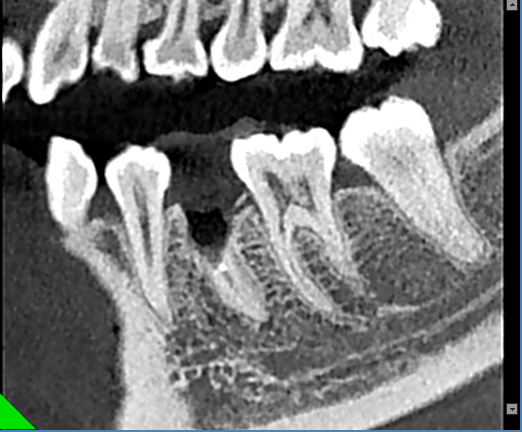

根管和牙周治疗过程中,提供牙根位置、角度、是否牙裂病变及下颌管、牙周围组织高清图像,以便于分辨治疗每个细节,做出精确诊断以及有效治疗方案。